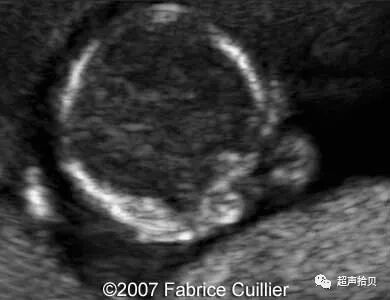

图3:位于颞窝的蛛网膜囊肿(C)。A:26周妊娠时横向超声扫查获得囊肿图像,彩色多普勒超声检查显示囊肿中没有流动。 B,28孕周产前核磁共振显示囊肿(C)位于颞侧窝(T2加权像[T2WI],横向平面)。 C,出生后1个月的产后MRI证实囊肿。(T2加权像[T2WI],横断面)